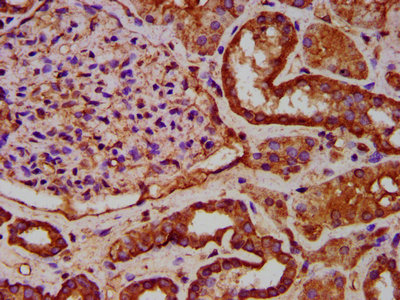

IHC image of CSB-PA011571LA01HU diluted at 1:600 and staining in paraffin-embedded human kidney tissue performed on a Leica BondTM system. After dewaxing and hydration, antigen retrieval was mediated by high pressure in a citrate buffer (pH 6.0). Section was blocked with 10% normal goat serum 30min at RT. Then primary antibody (1% BSA) was incubated at 4°C overnight. The primary is detected by a biotinylated secondary antibody and visualized using an HRP conjugated SP system.